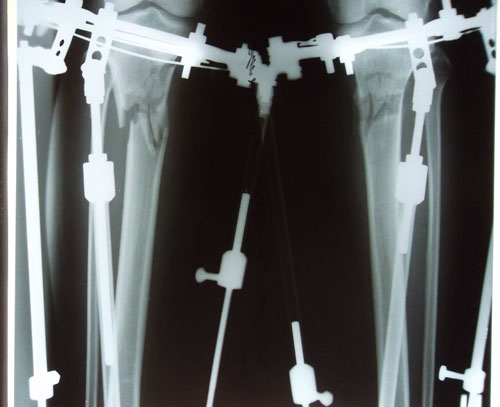

Re: МОЁ ПРЕОБРАЖЕНИЕ!

Дата операции 19.11. 2014г.

Дата снятия аппаратов 22.04.2015г.

Срок лечения 5 месяцев.